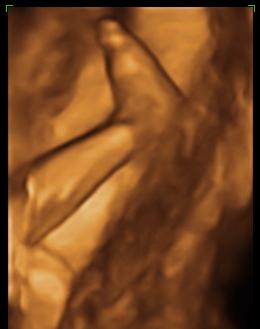

Kép Kortyolgatom a vizet

Kép ...é s ezzel rugdosom anyát. :)

De csodás!!!!!!! Azokkal a lábikókkal aztán jól oda tud küldeni anyucinak????!!!!! :wink: Édes ez a pici Dávid már most! :D :P :D